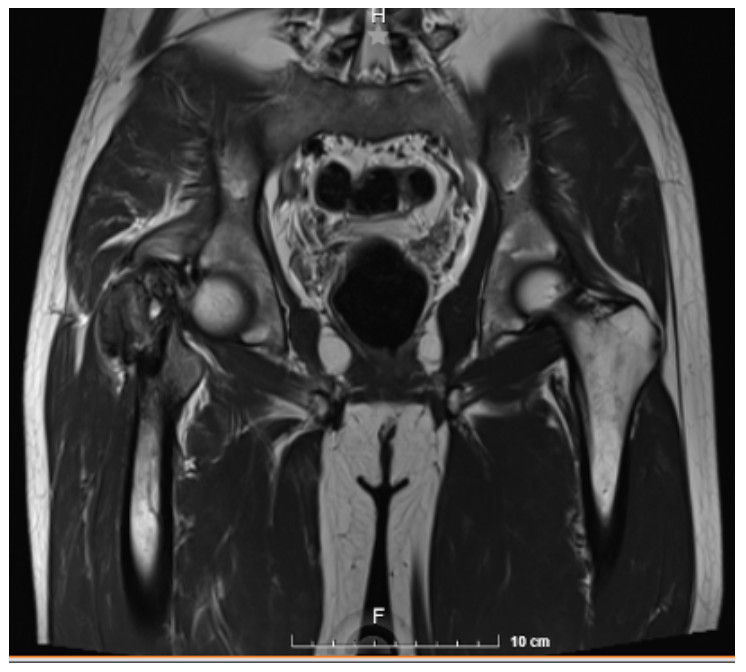

Hombre de 26 años de edad, que acude por dolor en cadera derecha de 10 meses de evolución que no mejora con ingesta de analgésicos. IDx. Quiste óseo.

Estudios de laboratorio: Hemoglobina 13.00 g/dL, hematocrito 37.5 %, LDH 298,000 UI/L.

Resonancia Magnética. Tumor en epífisis de fémur derecho, de localización excéntrica con componente sólido que condiciona edema de tejidos blandos. IDX. Tumor exofítico en fémur derecho.